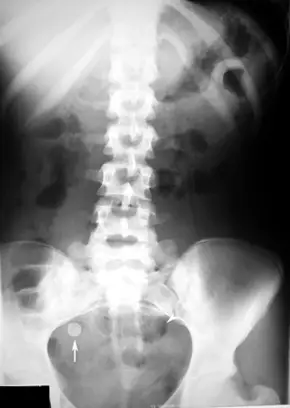

24 歲男子噁心及肚臍周圍不適隨後感到右下腹痛而至急診求診,腹部 X-ray 如圖所示,下列何者為較可能的診斷?

本題探討急性闌尾炎(acute appendicitis)在平片腹部 X 光上的特徵——appendicolith(闌尾糞石),以及典型的症狀模式(periumbilical pain 轉移至右下腹痛)與影像學的結合診斷。

平片腹部 X 光可見右下腹部(右側骼骨上方、闌尾分佈區域)一個約 0.5–2 cm 的圓形至橢圓形高密度影(箭頭所示),邊緣可見層狀鈣化環,符合 appendicolith 的典型影像呈現。周邊無明顯游離氣體或腸阻塞徵象,未見右上腹或膽囊區域灰白影提示結石,說明此鈣化體並非膽結石或腎結石。